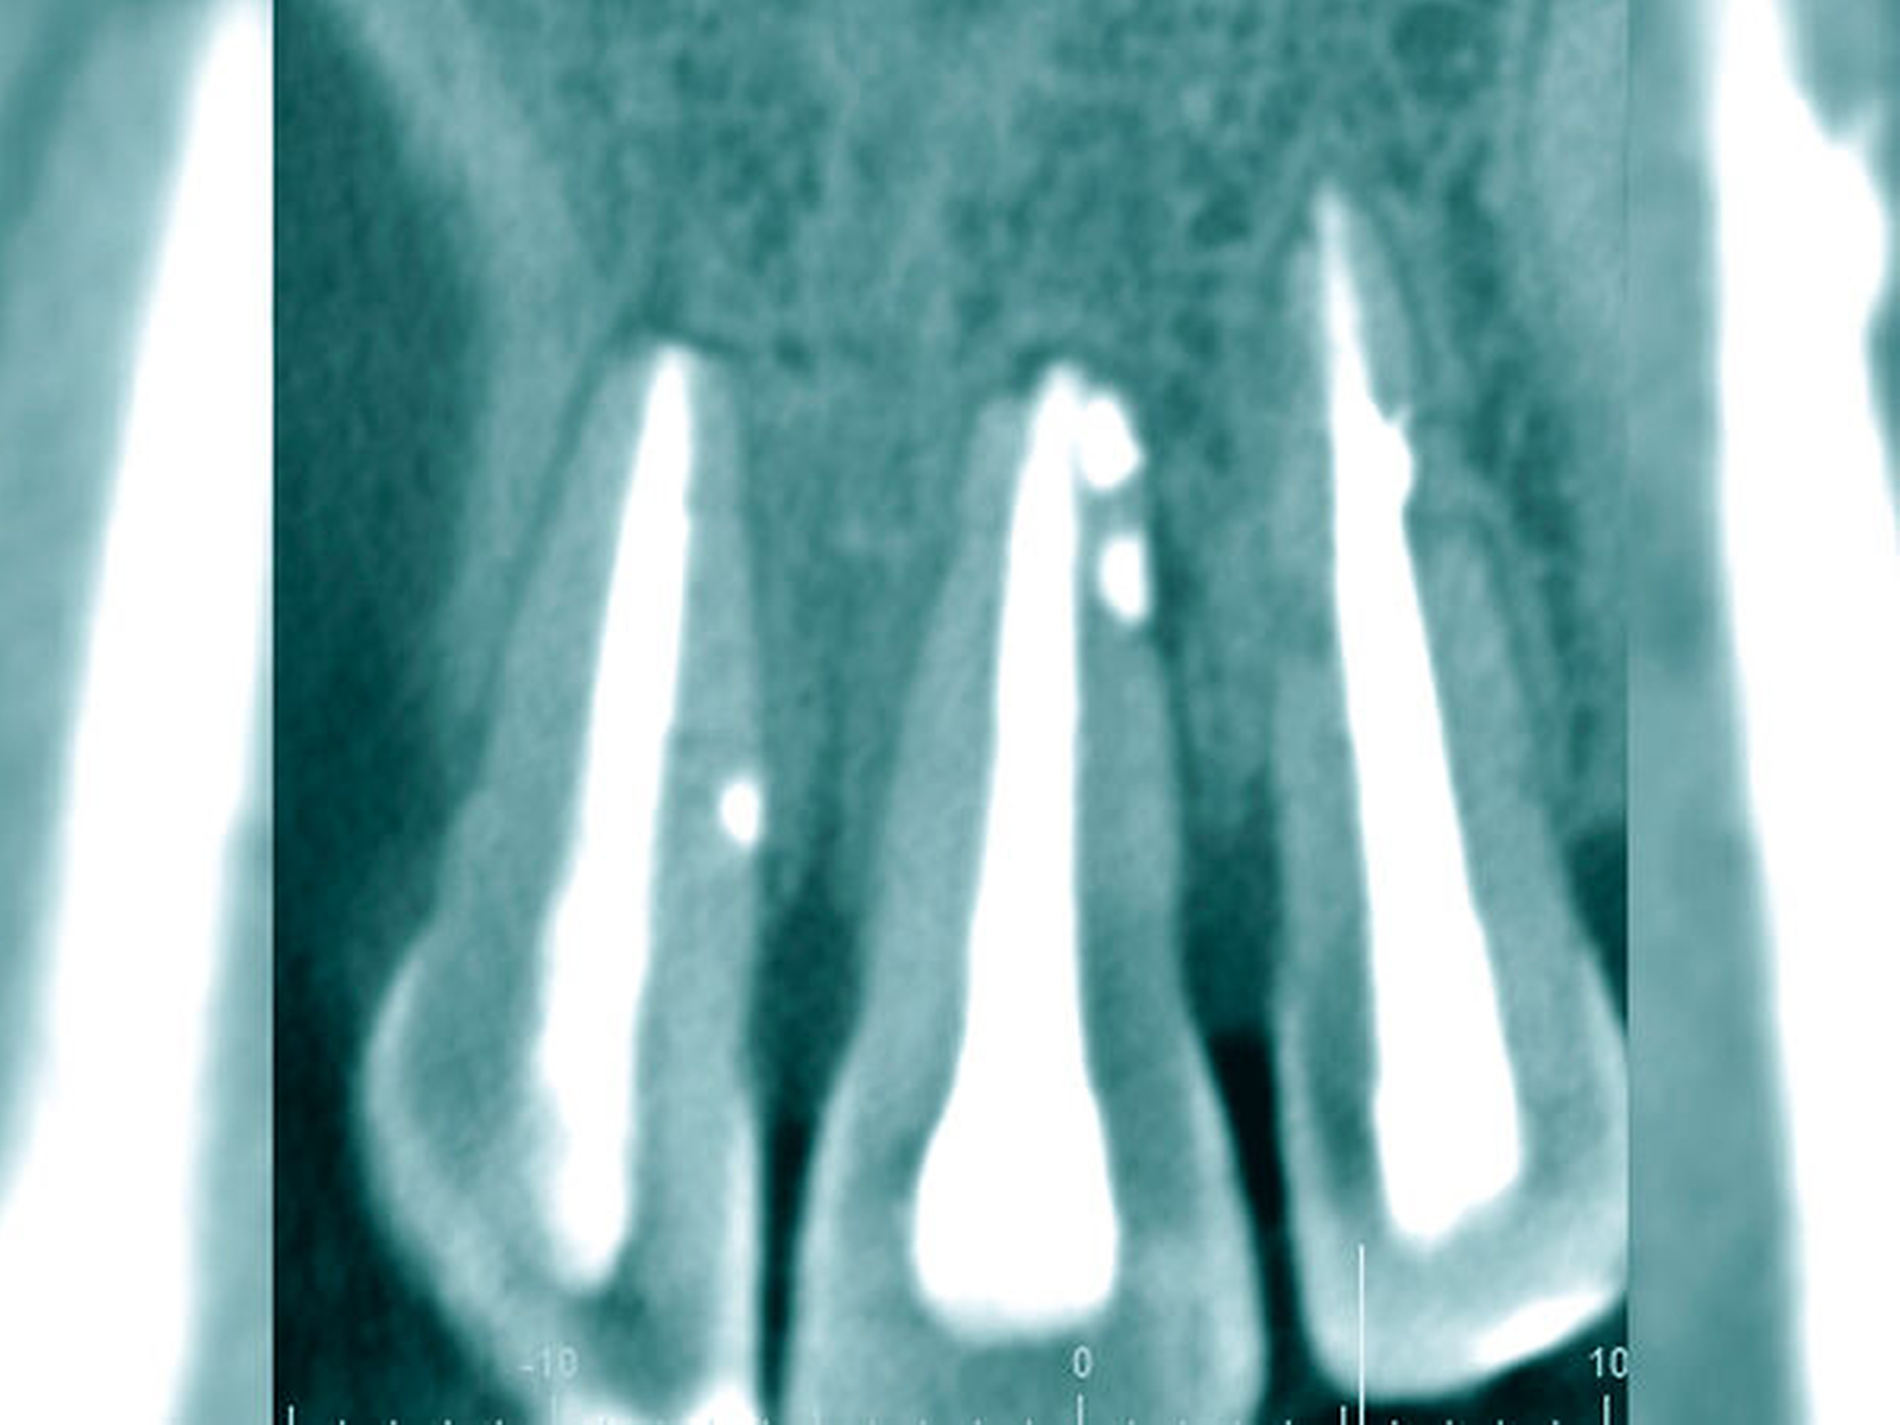

Die Schwierigkeit in der Therapie nimmt zu, wenn die Wurzelkanalkrümmung mehr als 30 Grad beträgt, der Krümmungsradius abnimmt (enge Krümmung) oder Mehrfachkrümmungen vorliegen [Duke et al., 2015; Pedulla et al., 2020]. Typisch für Mehrfachkrümmungen sind vor allem mesiale Wurzelkanäle unterer Molaren (Abbildung 4).

Sollte eine Konfluenz beider mesialer Wurzelkanäle am unteren Molaren vorliegen, kommt es zu einem abrupten Richtungswechsel und Instrumente können leichter frakturieren oder Stufen präparieren, so dass die Arbeitslänge nicht mehr erreicht werden kann.